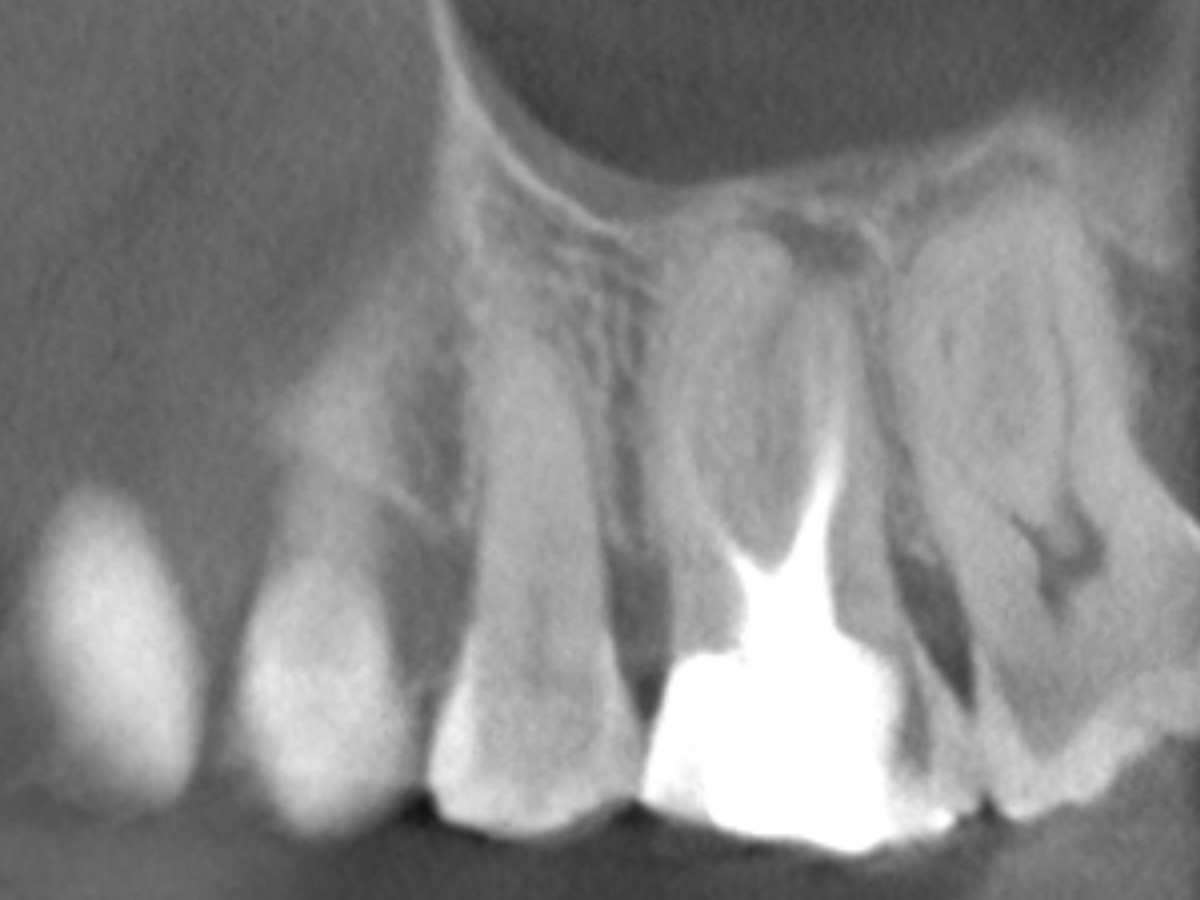

Die Arbeitslängen der Kanäle wurden mittels elektrometrischer Messung bestimmt und die Kanäle aufbereitet. Alle Kanäle außer dem palatinalen wurden bakteriendicht mit einer Sealer-basierten Wurzelfülltechnik (Guttapercha und TotalFill® BC Sealer) verschlossen.

Für den ovalen Querschnitt der palatinalen Wurzel wurde eine warm-vertikale Technik angewendet. Dazu wurde der Guttapercha Hauptstift mit dem B&L Alpha und einem Hitzeplugger (55/.08) in der Tiefe abgetrennt und kondensiert.

Mit dem B&L Beta wurde der restliche Kanal nach der Backfill-Technik schrittweise mit erwärmter Guttapercha aufgefüllt. Die abschließenden Röntgenaufnahmen zeigen das Ergebnis, das mit den kabellosen Systemen präzise und effizient umgesetzt werden konnte.

Abbildung 3

DVT sagittal